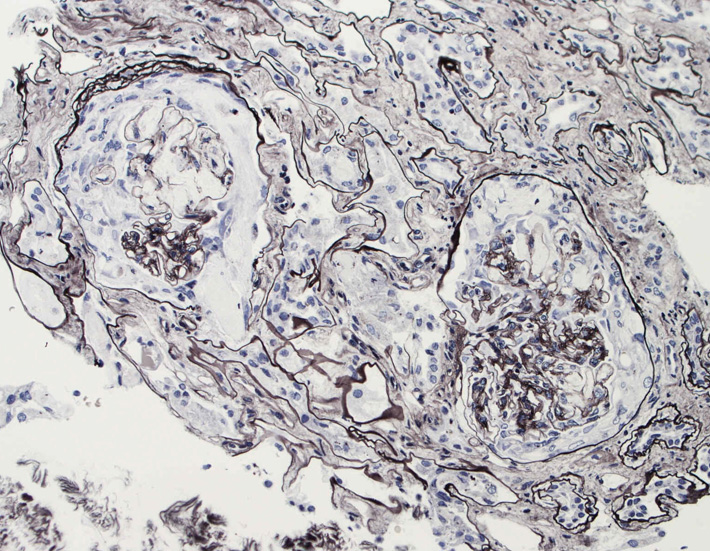

腎臓の病理組織所見-->壊死性糸球体腎炎

kidney04pas.jpg

kidney05.jpg

kidney06.jpg

Fig.03(PAS)Fig.04(PAM染色)Fig.05(PAM染色)